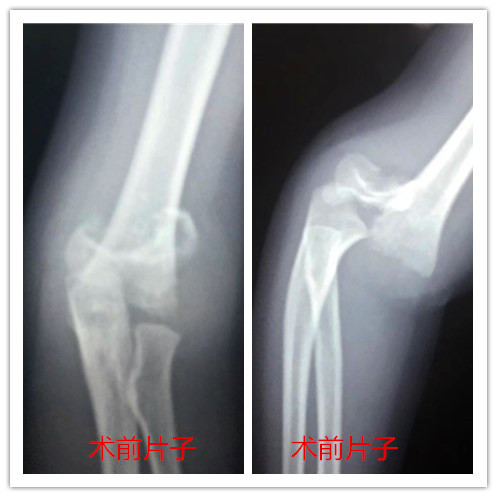

以下是我院上肢创伤科儿童肱骨髁上骨折

微创手术典型病例

2岁的小姑娘,因摔伤致右肘部肿痛,患儿右肘关节肿胀,来到我院进行治疗,DR片显示:右肱骨髁上骨折。患儿入院当天,即完善相关术前检查,在急诊全麻下顺利地为患儿进行了“右肱骨髁上骨骨折闭合复位经皮穿针固定术”,术后再对其石膏外托固定,患儿术后三天,病情恢复良好,出院转为门诊治疗(一周换药一次即可),6周后根据骨折愈合情况拔除内固定钢针,无需再次住院。

3岁的小男孩,因在家中玩耍时摔倒致右肘部,由家人送来我院治疗,DR片显示:右肱骨髁上骨折。患儿入院当天,即完善相关术前检查,在急诊全麻下顺利地为患者进行了“右肱骨髁上骨骨折闭合复位经皮穿针固定术”,术后再对其石膏外托固定,患儿术后三天,病情恢复良好,出院转为门诊治疗(一周换药一次即可),6周后根据骨折愈合情况拔除内固定钢针,无需再次住院。